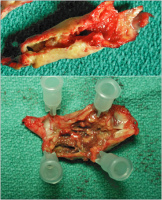

Eversionsendarteriektomie

Abbildung 3: Eversionsendarteriektomie